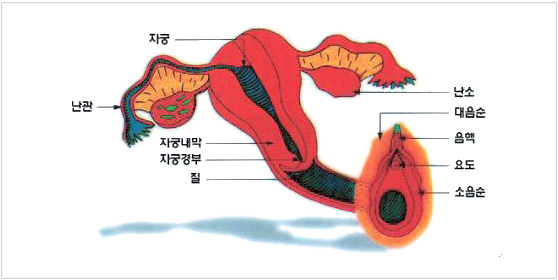

������ ���¸� �ڼ��ϰ� Ȯ���� �� �ֽ��ϴ�. ��ħ���� ������� �����ĸ� ����� ��ó���� ���� �ڱ� ������ ���¸� �����ϰ� �����ķ� ������ ���� �־��, �ڱó��ð��� ���ؼ� �ڼ��ϰ� �ڱó����� ���¸� �� ���� �־��.

�ջ���� �ڱó��� ���°� �����ǰ� �ֽ��ϴ�.